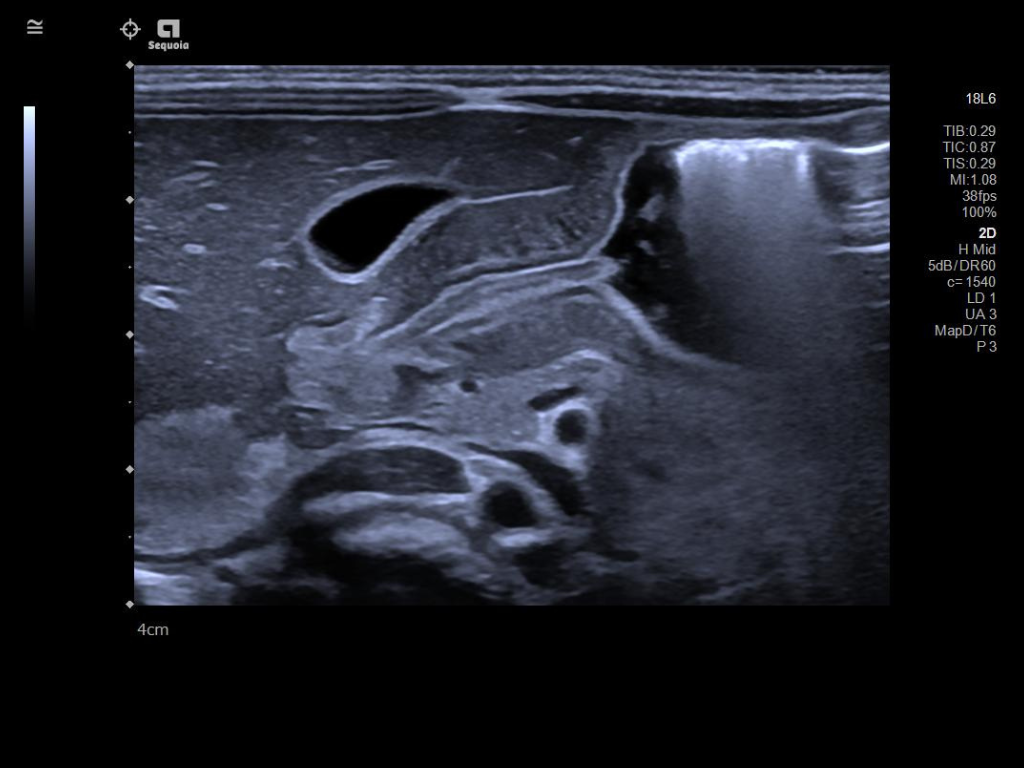

The ACUSON Sequoia is an advanced diagnostic tool that integrates cutting-edge technology and AI-powered applications to streamline diagnostic processes. This system is designed to cater to patient-specific needs, ensuring accuracy and efficiency in various clinical settings such as Radiology, OB/GYN, Shared Service and beyond.

The latest updates on ACUSON Sequoia use the power of groundbreaking AI for abdominal cases, includes advanced breast visualization to deliver new levels of image quality confidence, and tackles the toughest challenges in musculoskeletal imaging, all while saving your team from needless strain and pain.

Boost your clinical confidence with a system designed to enhance your expertise. The ACUSON Sequoia gives you the power to know more by maximizing the sensitivity and depth of your scans, while reducing variability across patients, systems and users.

ACUSON Sequoia’s InFocus imaging architecture eliminates the need for conventional focal zones to create a fully focused image faster than conventional systems. Our InFocus technology applies to all imaging transducers and exam types giving you consistent imaging across clinical segments. Some of the benefits are:

A clearer, deeper perspective with optimal acoustics for each clinical use case. Expand your assessment with advanced tools that take ultrasound beyond its traditional role.